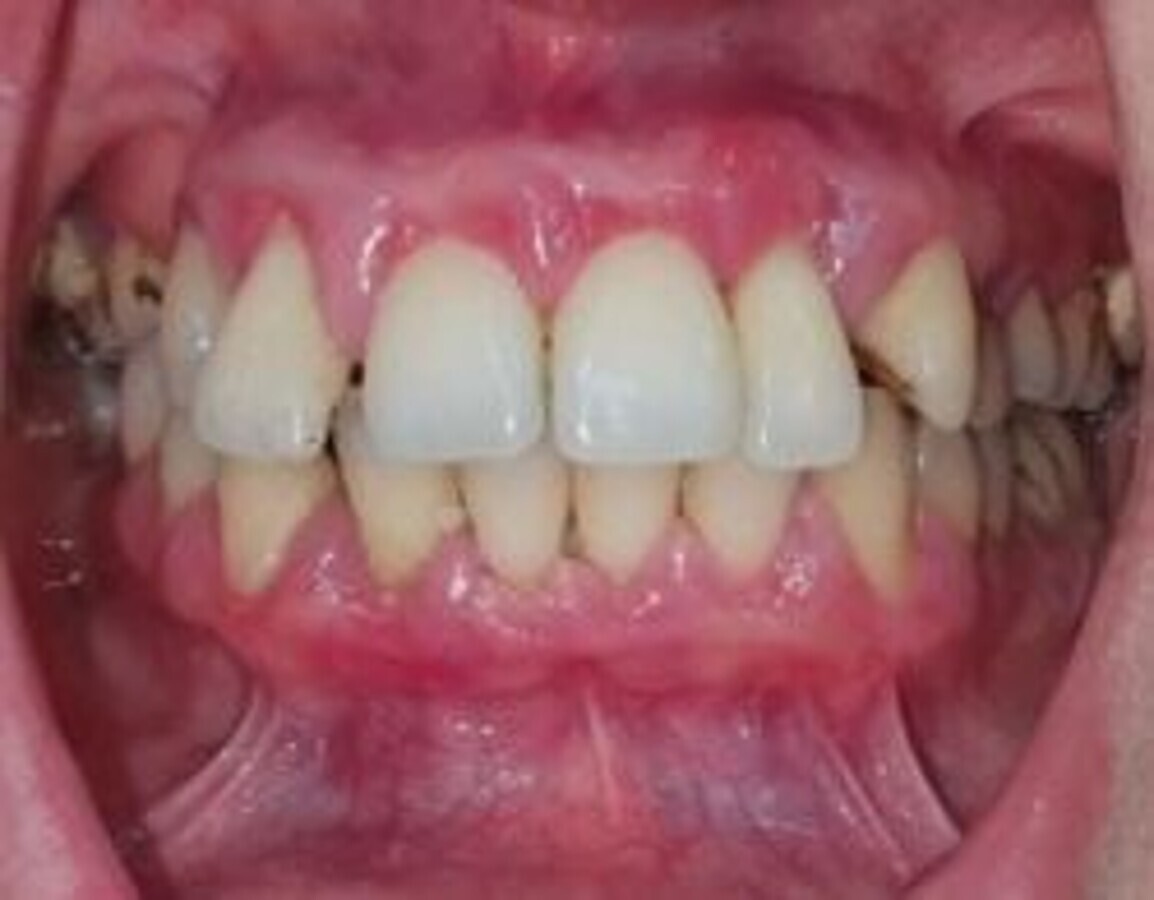

Fig. 1 : Influence des hormones sur le parodonte : gingivite chez une femme au sixième mois de grossesse noter la gencive rouge, volume augmenté et épulis entre La 22 et la 23